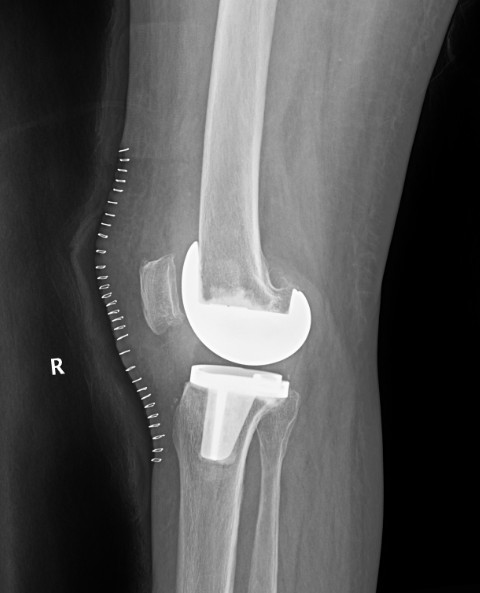

病例二:患者女性,82歲。主因“右膝疼痛10年伴加重、活動(dòng)受限半個(gè)月”入院。入院前右膝痛時(shí)好時(shí)壞,疼痛劇烈時(shí)無法站立。

患者術(shù)前全長

患者術(shù)后

患者術(shù)后全長